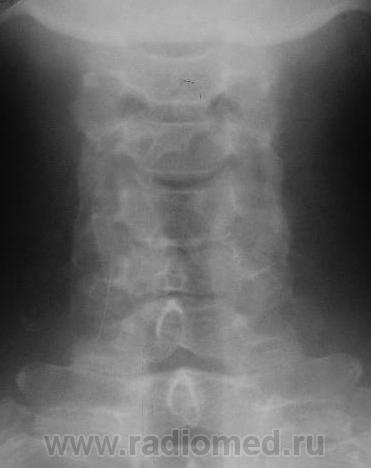

Уважаемые коллеги! Данные снимки произведены вне какой-либо связи с травмой или жалобами на боли. Просто такая картинка встречается довольно часто. Как Вы для себя интерпретируете такие деформации задних углов тел позвонков? Могут ли они вызывать неврологические жалобы? Является ли это следствием остеохондроза? На мой взгляд, на краевые костные разрастания в обычном их понимании это мало похоже.

На рентгенограммах шейного отдела позвоночника в 2-х проекциях определяется сглаженность физиологического лордоза,  снижение высоты межпозвонковых дисков на уровне С4-5 2 ст., С5-6 1 ст., уплотнение замыкательных пластинок, скошенность передневерхних углов С3-7, деформация тела С4, передние осеофиты тел С4-С6, задние С5-6, остеофиты унковертебральных сочленений. Явления субхондрального склероза межпозвоночных суставов.

Заключение: Остеохондроз шейноо отдела позвоночника 2 ст. Спондилоартроз.

Норма.Вариант строения лимба тел позвонков.Выпрямленность лордоза может быть следствием укладки. Диаметр корешка и диаметр спинно-мозгового отверстия в шейном отделе позвоночника соотносяться как 1:16 , если не ошибаюсь, т.е. 16-кратный запас прочности, для компенсации заложен природой в случае подобных конфликтов(компрессия корешка).Корешковые синдромы на шейном уровне редкость.Тем более клиники нет. О чём вести речь.Скверно,коллеги, когда мы свои умозрительные представления искренне подаём как истину.